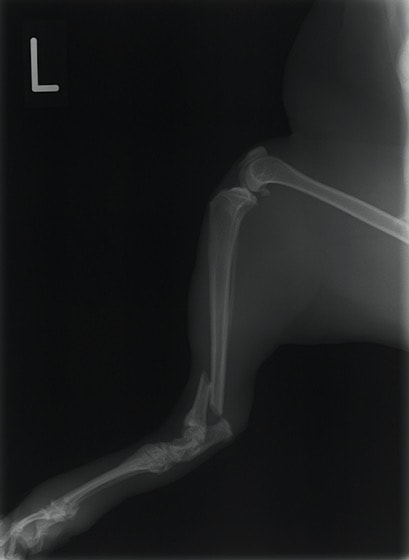

ペルシャ猫 11ヶ月齢 雄

他院にて左大腿骨遠位の成長板骨折(salter-harrisⅠ型)が認められており、治療相談を目的として来院。当院にて、キルシュナーワイヤーを用いたピンニングにより骨折部位の整復を行いました。術後の経過は良好で、現在も経過観察中です。

術前レントゲン

術後レントゲン